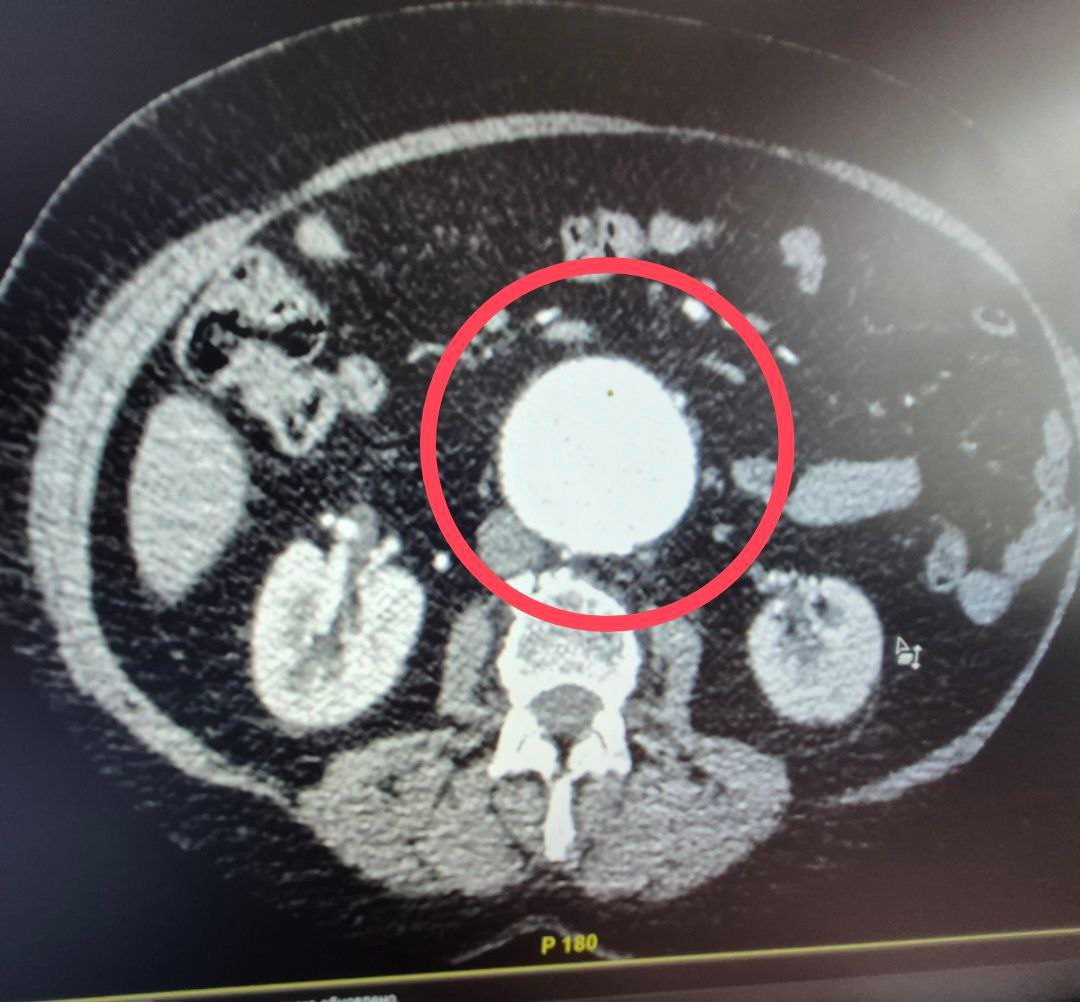

Как пояснили медики, к ним поступила 60-летняя пациентка с крайне опасным диагнозом — мешотчатая аневризма брюшной аорты.

«Это патологическое расширение главного сосуда организма, которое в любой момент может привести к внутреннему кровотечению. Случай действительно уникальный — аневризма брюшной аорты считается «бомбой замедленного действия», а мешотчатая форма особенно опасна из-за риска мгновенного разрыва.

Ситуация была настолько серьезной, что в проведении операции женщине отказали даже в областных клиниках», — пояснили в больнице.